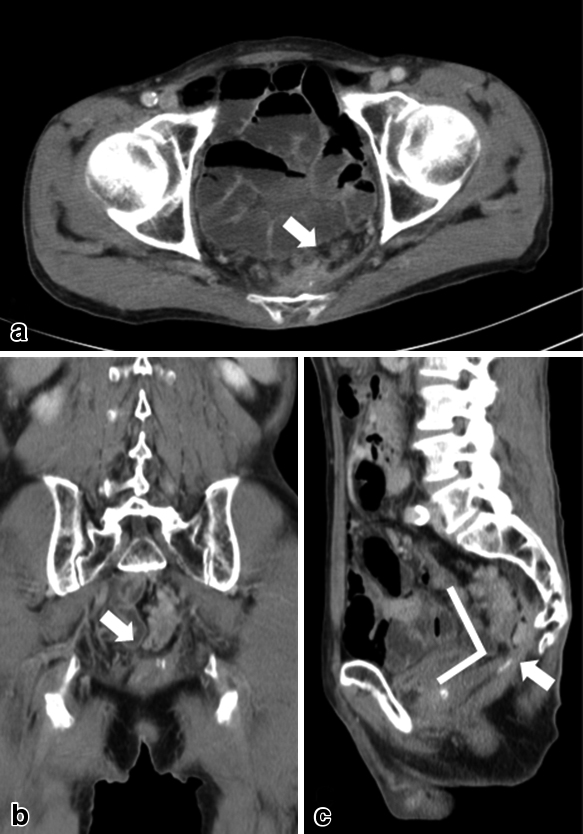

Study before Yamanouchi method. a, b) Contrast-enhanced CT showed the occlusion of rectal anastomosis (arrows). c) The occlusion area was bent like the angle.

治療:本症例では閉塞部が屈曲しており,内視鏡的切開では穿孔の危険性が大きくなると判断した(Fig. 2).また,術後縫合不全による骨盤内膿瘍治療後のため,骨盤内は高度の癒着が予測され,吻合部閉塞部切除,再吻合は手術侵襲が大きく,血流不全から再び縫合不全を起こす可能性も高いと考えられた.このため2014年1月,出血・感染・穿孔などのリスクが小さく,時間を要してもより安全な方法として,磁石圧迫吻合部狭窄解除術(第2山内法)を行った.なお,治療については患者・家族への説明を十分に行ったうえで同意を得た.